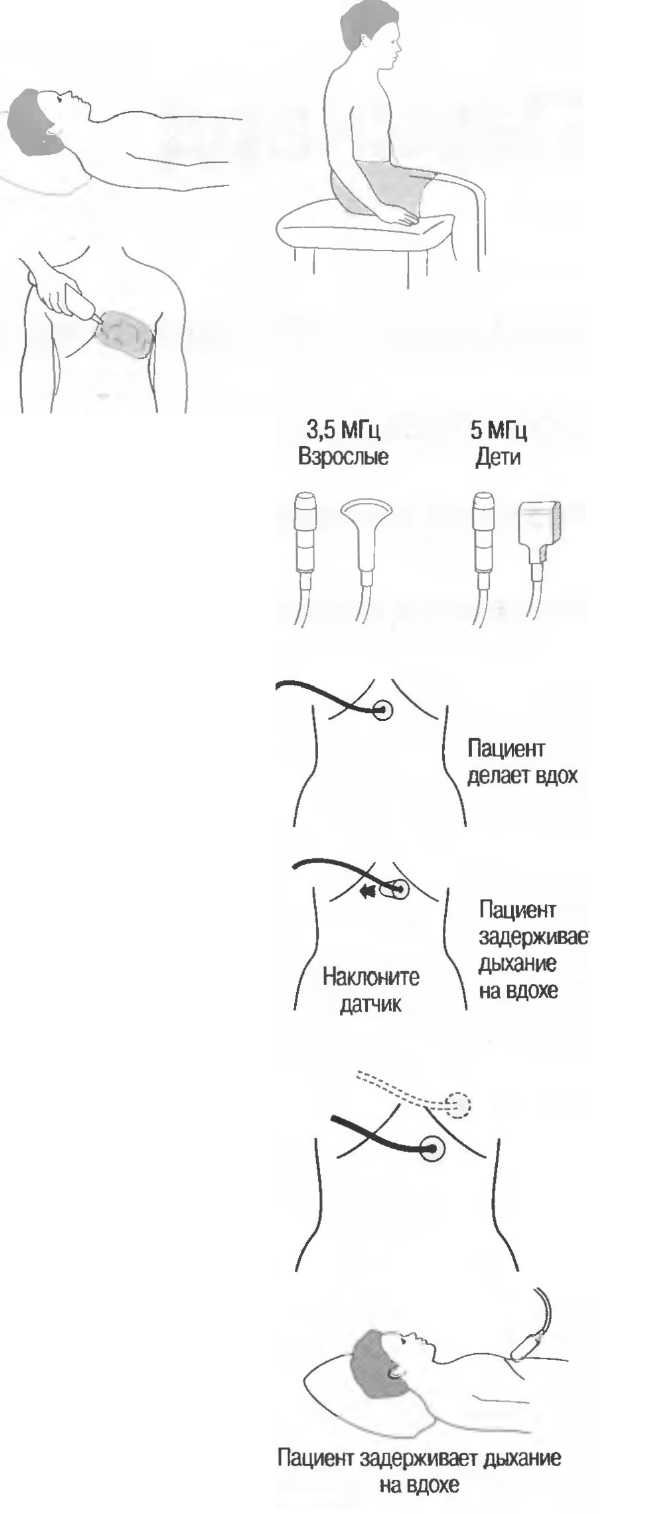

Затухание

Ткани тела поглощают и рассеивают ультразвук по-разному. Высокие частоты поглощаются и рассеиваются (гасятся) в большей степени, чем низкие. Поэтому, чтобы достичь более глубоких тканей, необходимо использовать более низкие частоты, так как менее вероятно, что эти волны затеряются при прохонодении через ткани. На практике оптимально использовать частоту около 3,5 МГц для глубокого сканирования у взрослых и частоту 5 МГц и выше для исследования более худых пациентов или детей. Частота 5 МГц и выше используется для исследования поверхностных органов у взрослых.

Выбор соответствующего датчика

Наилучшим датчиком для общей практики является конвексный датчик с частотой 3,5 МГц с фокусировкой на расстоянии 7-9 см. Если такого датчика нет, необходимо наличие линейного секторного датчика с частотой 3,5 МГц. При необходимости исследования детей и худых взрослых желательно дополнить набор датчиком с частотой 5 МГц с фокусировкой 5-7 см.

1. Ультразвуковые исследования в акушерстве. Для общих исследований в акушерстве используется линейный или конвексный датчик с частотой 3,5 или 5 МГц с глубиной фокусировки на 7-9 см. Если закупается только один датчик, выбирайте датчик с частотой 3,5 МГц. Датчик с частотой 5 МГц предпочтителен на ранних сроках беременности. В поздние сроки беременности лучше использовать датчик с частотой 3,5 МГц.

2. Ультразвуковые исследования в общей практике. Если проводятся исследования в верхней части живота и таза у взрослых, в том числе и акушерские исследования, предпочтительнее выбор секторного или конвексного датчиков с частотой 3,5 МГц с глубиной фокусировки на 7-9 см.

3. Ультразвуковые исследования в педиатрии. Для детей необходим датчик с частотой 5 МГц с глубиной фокусировки на 5-7 см. При исследовании мозга новорожденного используется секторный датчик с частотой 7,5 МГц с глубиной фокусировки на 4-5 см (этот датчик также используется для исследования яичек и структур шеи у взрослых).